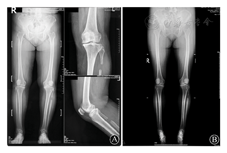

患者,女,64岁,身高161 cm,体重85 kg,体重指数(BMI)32.8 kg/m2,以左膝疼痛并加重3年余于2018年9月11日至复旦大学附属华东医院骨科就诊。患者3年前左膝疼痛,运动后疼痛,休息可部分缓解。后患者出现疼痛加剧,步行距离缩短,经保守治疗无效后,于2017年4月10日在外院以"左膝关节骨关节炎"行"左侧腓骨上端截骨术",术后对症治疗。患者诉术后症状未有明显改善,日常步行距离约200 m,视觉模拟评分(VAS)8分,站立位及最大下蹲位状态见图1。2018年7月17日(不均匀沉降术后15个月)于外院复查X线(图2 A)。门诊时患者左膝关节屈曲120°,伸直3°,关节间隙内外侧均有压痛,内侧为重,股四头肌抗阻试验(+)。患者为求进一步治疗,于2018年9月17日收住入院。

住院期间完善患者WOMAC问卷、KSS膝关节评分、Lysholm膝关节评分、SF-36生活质量评分(表1),同时完善各项术前检查。实验室检查未见明显异常,排除自身免疫性疾病或代谢障碍性疾病导致的关节炎。2018年9月17日(不均匀沉降术后17个月)于本院行站立位双下肢全长位片(图2 B),提示:"双侧膝关节骨质边缘骨质增生影,胫骨髁间棘增生变尖、肥大,双膝关节内侧关节间隙变窄,左侧为甚。左侧腓骨上段局部骨质缺损。余所示诸骨未见特殊"。图2中不均匀沉降术后15个月、17个月截骨高度7.5 cm,截骨长度2.4 cm,其他数据测量见表2。术前完善左膝关节MRI(图3),提示:左膝周围诸骨位置关系正常,股骨、胫骨、髌骨边缘增生变尖,膝关节及髌骨关节间隙变窄,关节面毛糙,关节面下见小斑片状骨质吸收灶及骨质水肿,左膝内外侧半月板前后角内信号欠均匀,可见小片状稍高信号影,内侧半月板及外侧半月板前角内异常信号延伸达关节面,前交叉韧带肿胀,股四头肌肌腱及髌韧带局部稍肿,后交叉韧带及双侧副韧带形态信号尚如常,关节腔及髌上囊内见少-中等量长T1长T2信号积液影,关节滑膜增厚。左膝周围软组织肿胀,髌下脂肪垫局部明显肿胀。MRI诊断结论:左膝退变:骨质增生;关节面下散在骨质吸收及骨质水肿;半月板变性,内侧半月板及外侧半月板前角撕裂;前交叉韧带肿胀,股四头肌肌腱及髌韧带局部稍肿;关节腔及髌上囊内少-中等量积液,关节滑膜增厚;左膝周围软组织肿胀,髌下脂肪垫局部明显肿胀。见腘窝囊肿。